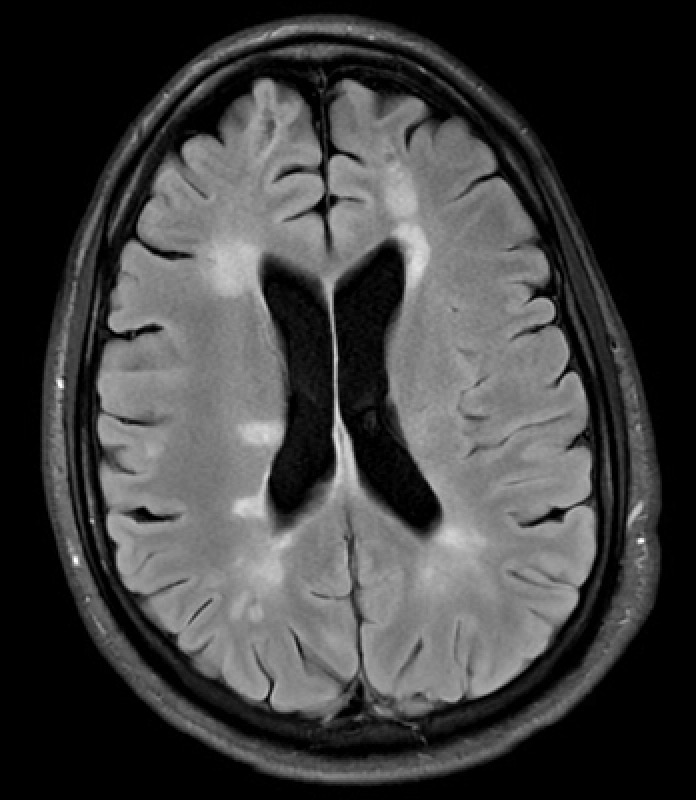

MRI provides high-resolution images using magnetic fields and radiofrequency pulses, making it the modality of choice for most neurological diseases.

Key Sequences:

T1-weighted: anatomy, structural detail, post-contrast imaging

T2-weighted: edema, inflammation, and demyelination

FLAIR: suppresses CSF to highlight periventricular lesions (e.g., MS)

DWI/ADC: detects acute ischemia

SWI: sensitive to blood products and calcification

MRI: multiple sclerosis, tumors, ischemic stroke, encephalitis, demyelination